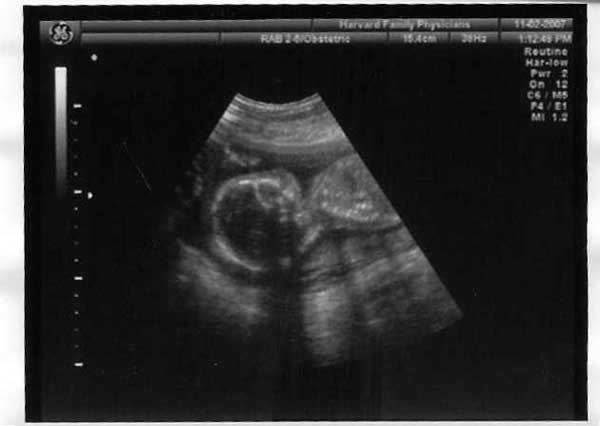

HI how is everyone doing? I'm so glad that you all stay up to date on news letter (those of you who do) so Zeke and I can see how everyone is growing and doing. We are doing well. I am 19 weeks and two days along, and thus far my due date is still March 27 2008. I went and saw the Dr. today and she is pretty sure she knows what the sex of the baby was. After checking, poking at my stomach to get the baby to move, and then reposition of the camera she figured out that we are most likely having a GIRL!!!!

Hasn't she grown?!?! Now the last time we went to the Dr. (Oct 12, 2007) the baby wouldn't come out of the fetal position long enough for the Dr. to see so we had to wait a month to find out but it was well worth the wait. She weights 12 oz, and has been checked for Down syndrome and other visual birth defects, none were seen. Thus far we have been able to hear the heart beat and see her four chamber heart in action. That was really neat! So she is doing well. I have gained about 15 lbs and am feeling for the most part really good. My patience with people at work is a little short but all in all I'm handling things well. We have started touring hospitals to see where we would like the even to take place so far we have toured one hospital and it was pretty impressive. They have a lock down unit (something that I am unsure if it is standard or only some places offer and feature) Zeke liked it because there is a fold out bed in the delivery room. Yes I informed him it didn't matter as he wouldn't be using it.